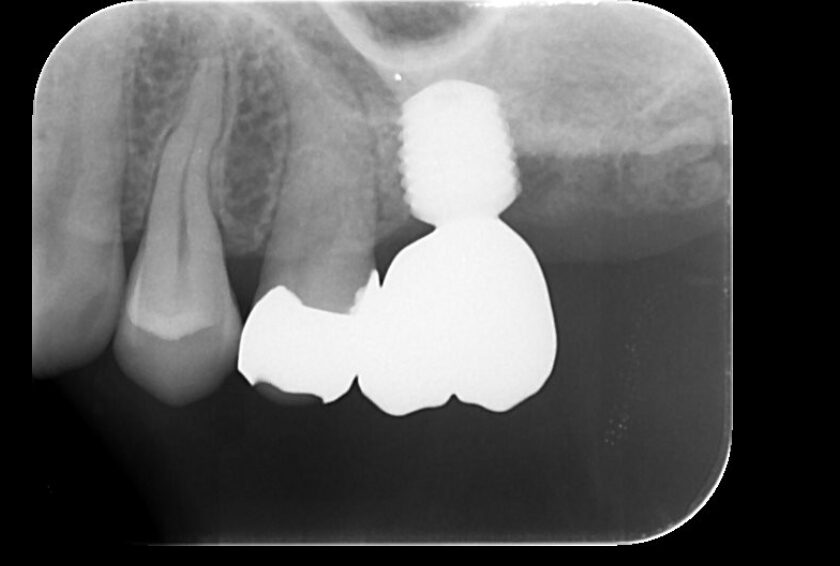

SET後のデンタルX線写真

術前

術後